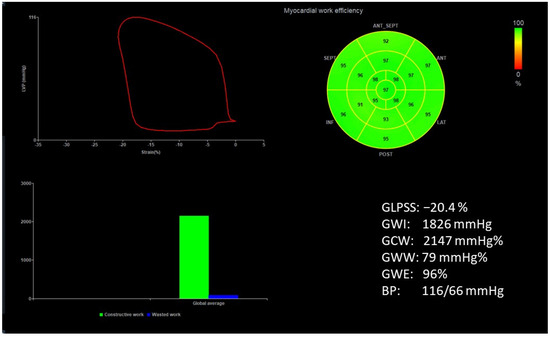

Figure 1 and Figure 2 show two contrasting examples (a healthy person and a patient after myocardial infarction and left bundle branch block) of STE curves with GLPSS, LVEF and LV pressure–strain loops and results of GWE for all LV segments.

Figure 1.

An example of echocardiography of a 30-year-old healthy male. A set of individual longitudinal strain curves for all segments shown in different colors, with the average curve shown as a white dotted line, a bull’s eye of segmental longitudinal peak systolic strains and a summary of global longitudinal peak systolic strain (GLPSS) are shown in the top panel. The LV pressure–strain loop with the bull’s eye representation of myocardial work efficiency for each of the segments and a summary of all myocardial work indices are shown in the lower panel. Abbreviations: GLPSS—global longitudinal peak systolic strain, EF—ejection fraction, GWI—global myocardial work index, GCW—global constructive work, GWW—global wasted work, GWE—global work efficiency, BP—blood pressure.